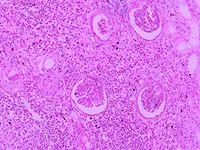

急性肾盂肾炎 病变可为单侧或双侧,局限或广泛,可轻可重,轻者仅累及肾盂粘膜。重者肾脏肿大,切面可见粘膜充血溃疡,小脓肿形成。如伴梗阻,则肾盏增宽,少数严重患者,其肾乳头及锥体部可见坏死,坏死组织随尿液排出称坏死性乳头炎,镜下可见肾间质水肿,嗜中性粒细胞浸润。

慢性肾盂肾炎 肾盂及肾盏有慢性炎症表现。肾盂扩大、畸形,肾皮质及乳头部有瘢痕形成,肾脏较正常缩小,两侧病变常不对称,肾髓质变形,肾盂肾盏粘膜及输尿管管壁增蚅,严重者肾实质广泛萎缩。